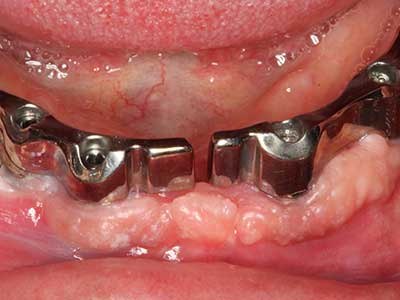

Пиезохирургията има допълнителни предимства при събиране на костни блокове. В допълнение към високата прецизност при остеотомията, описана по-горе, употребата на фините режещи накрайници значително намаляват загубата на материал. Голяма загуба на материал по време на събиране може да се очаква с дебелите накрайници, особено при употреба на борери Линдеман (Lakshmiganthan, Gokulanathan et al. 2012). Базалното разделяне, което е необходимо, особено за присадка на блок при ретромолар, е улеснено от специално създадени правоъгълни триони. В резултат на това, пиезохирургията е разглеждана като прецизна, улеснена и безопасна процедура за събиране на костни блокове в ретромоларното пространство (Happe 2007) (Фиг. 1-12).

Индикация: Костно разделяне/ шиниране?

Костната тъкан е не само минерализирана структура, тя съдържа и съществено количество колагенови влакна. Това означава, че тя има не само добра компресивна сила, но и известна степен на гъвкавост, която може да се възприеме като предимство при извършване на костна аугментация. В класическата процедура по разширяване чрез костно разделяне, атрофиралият алвеоларен гребен е разделен надлъжно и внимателно разширен след достигане на подходящата остеотомна дълбочина (Фиг. 13-16), в идеалния случай без допълнително отстраняване на периостеума (Brugnami, Caiazzo et al. 2014, Stricker, Fleiner et al. 2014). Системите с винт и пластини с увеличаване на разстоянието при разширяване са доказали ефективността си при разделяне на двете костни ламели, оставайки под прага на фрактурите. В общи линии, оставащата ширина на костта от поне 3–4 mm е задължителна (Chiapasco, Zaniboni et al. 2006), за да се гарантира добра гъвкавост и достатъчно костно покритие за бъдещото поставяне на импланти. Ако е необходимо, вертикалната остеотомия на едната или двете страни може да подобри гъвкавостта. Комбинацията с допълнителни техники за аугментация, особено в букалната страна, е описана като алтернатива на класическата техника.

Процедурата по разделяне е атравматична и няма голяма загуба на пространство, използвайки пиезотриони, и няма значителна разлика между импланти в разделени челюсти и импланти в алвеоларния гребен без костен дефицит (Chiapasco, Zaniboni et al. 2006, Danza, Guidi et al. 2009). Въпреки това, важно е да има достатъчно и продължително охлаждане, особено при ограничено и дълбоко разделяне, за да се избегне термичен стрес в апикално-остеотомните зони.